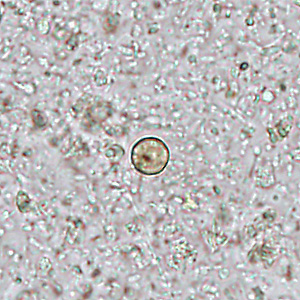

Several people developed gastrointestinal symptoms of watery diarrhea, nausea with vomiting, and low-grade fever approximately 1 week after attending a catered event. Stool specimens were collected for laboratory testing which included a formalin-ethyl acetate concentration with brightfield wet mount examination. Figures A–D show what was observed at 400x magnification in all of the specimens. The objects of interest shown ranged in size from 8 to 10 micrometers What is your diagnosis? What other test(s), if any, would you recommend?

Figure A